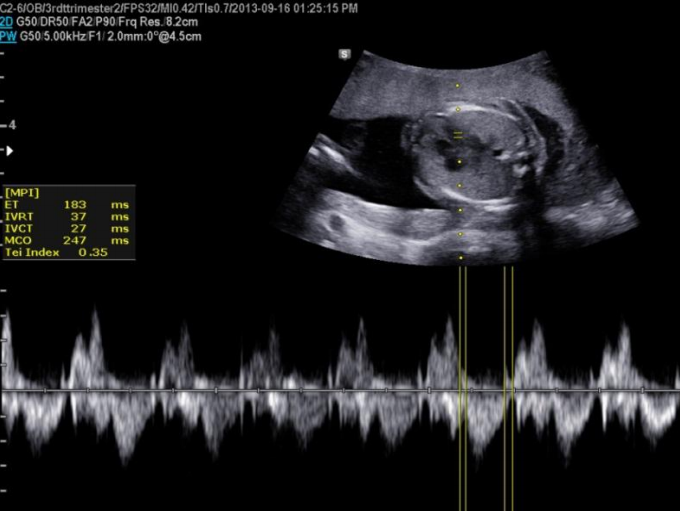

MPI胎心心肌做功指数(左心室)

又称Tei指数,是指心室等容收缩期时间(ICT)与等容舒张期时间(IRT)之和与射血时间(ET)的比值。

是全面评价心脏的整体收缩与舒张功能及反应胎儿宫内安危的指标之一。

MPI一键操作实现智能识别及自动测量,具有良好的可靠性和重复性,结果准确。